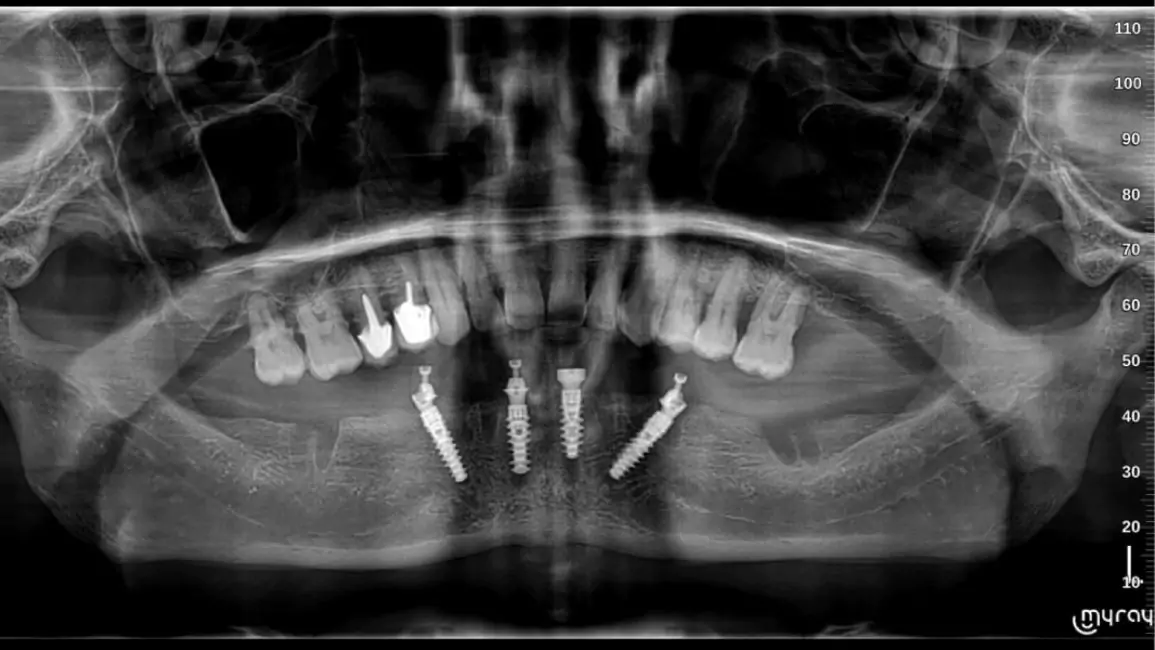

What is the procedure of full mouth dental implants?

The procedure of Full Mouth Dental Implants involves, extraction of teeth or root of the existing teeth if any, CBCT Scans and X-ray, Planning of implant placement, procedure of Implant placement, healing, temporary prosthesis and then a final prosthesis restoration, giving a perfect smile, functionality and appearance.

How are dental implants replaced in the mouth?

Implants are placed based various factors, prominent being 0the bones density for implant placement, every procedure is done using the advanced technology, such as CBCT guided implant placement, while also Implant torque is considered crucial. These all things are considered to place implants strategically to support Full Mouth Teeth Replacement, for functionality, durability and aesthetics.